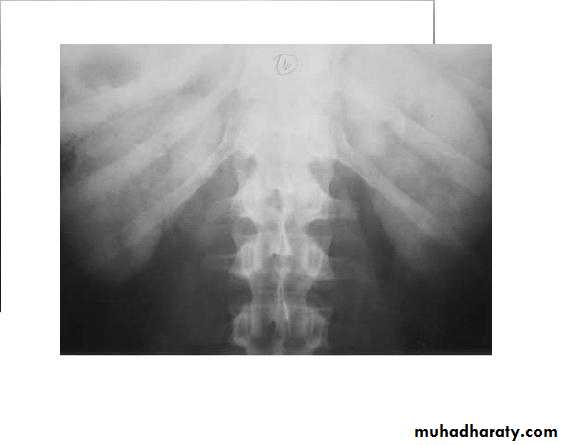

Laterally displaced ureters